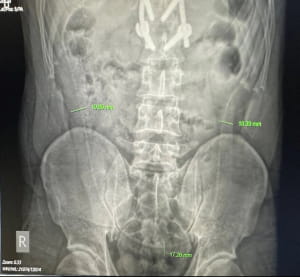

У лікарні Viet Duc рентгенівське обстеження виявило всередині пацієнта вугра довжиною 65 см, якого він засунув того ж дня, 27 липня. Знімок показав "довгу структуру", що простягалася через увесь живіт.